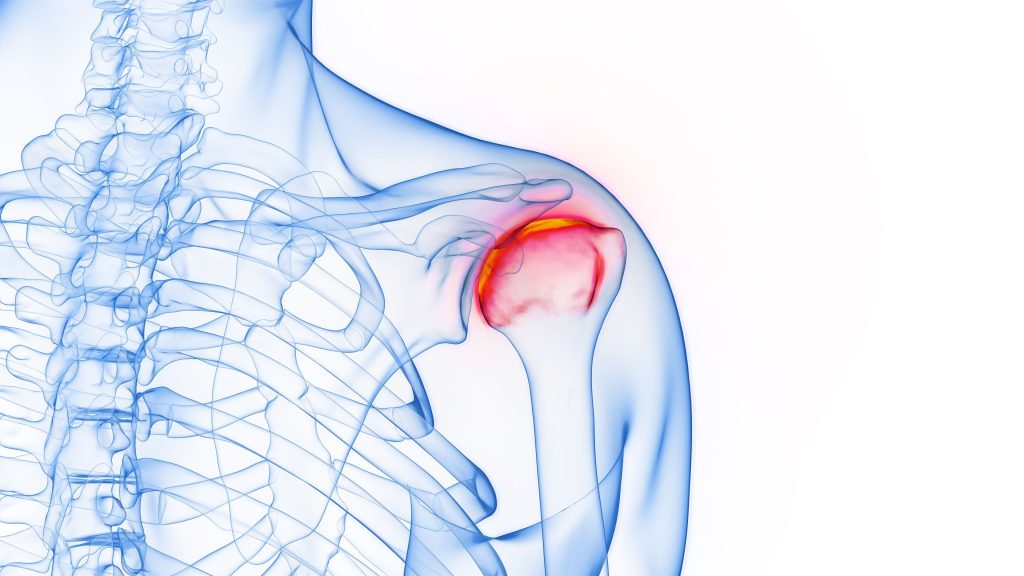

Interesting facts Orthopaedic is a word derived from the Greek “Ortho” and “Pais” or “straight child”. This is because it was originally used as a word to describe children with spine and limb deformities. Nowadays, Orthopaedics is more commonly used to describe the study and medical treatment of the musculoskeletal system, namely the bones and […]